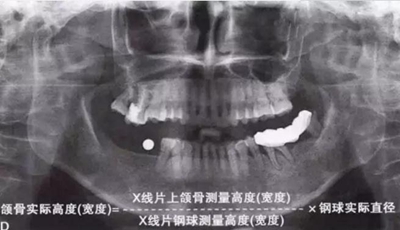

如何通過曲面斷層片測量出相對準(zhǔn)確的數(shù)據(jù)?告訴大家一個很實用的方法,就是利用小剛球作為參照。

將小剛球放到口內(nèi)時拍攝曲面斷層片,拍攝后得到的結(jié)果就是這個樣子的:

5.jpg

因為小剛球的直徑是固定的,通過測量片子上小剛球的直徑,就能算出曲面斷層片的放大率,然后就能算出真實的骨高度了,這是一個很不錯的方法。